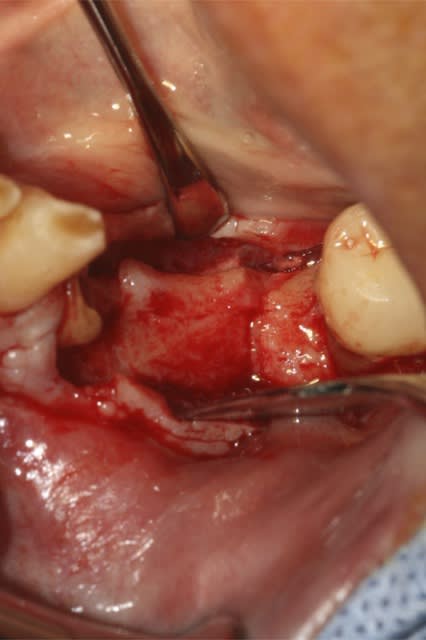

image1: incision verticale + décollement du lambeau de proche en proche

image 2: prélèvement Ramique

image 3 et 4: découpe d'une fine lame allant servir de toit